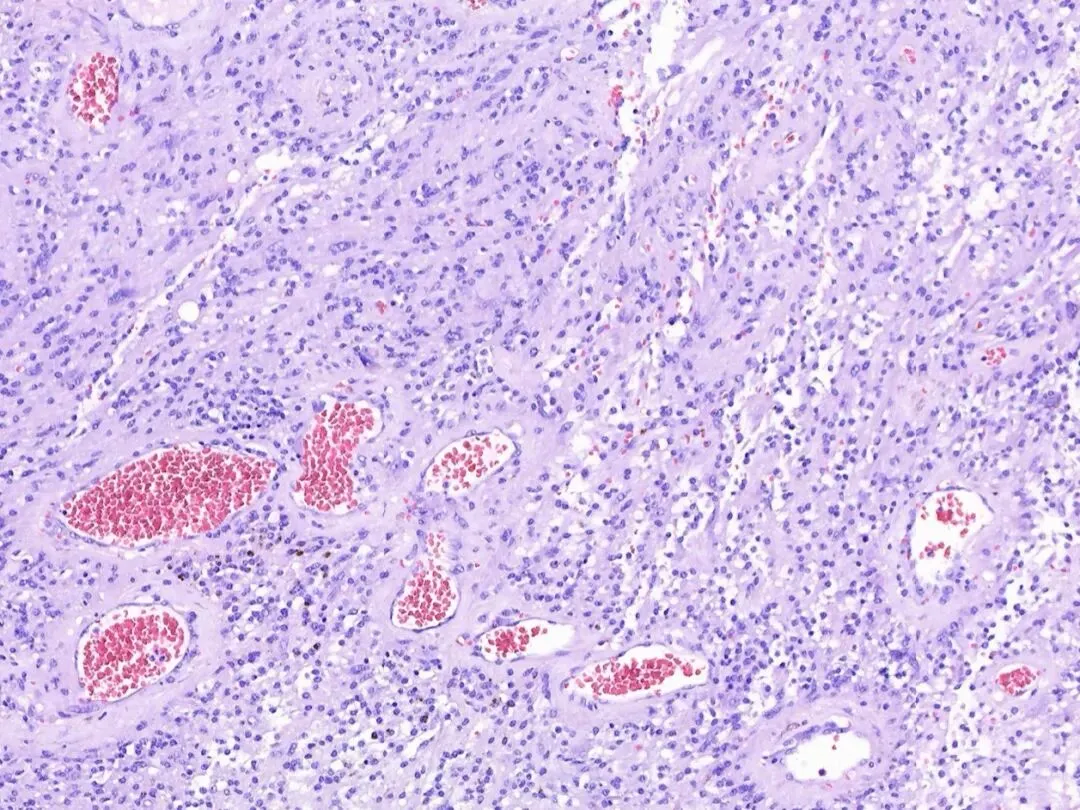

低倍镜下观察隐约可见致密区和疏松区,但不明显。

这部分区域细胞相对密集,如下图:

下面是相对疏松的区域。